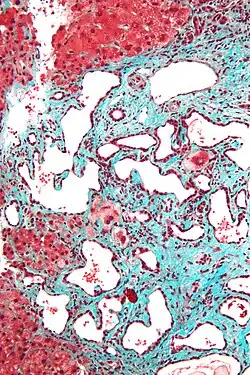

Histopathology of a bile duct hamartoma, high magnification, H&E stain. It shows typical features of bile duct hamartoma: Small to medium sized, irregularly shaped bile ducts lined by bland cuboidal epithelium (may also be flattened). Prominent intervening collagenous stroma. Bile ducts containing eosinophilic debris (may also contain inspissated bile) -

Micrograph of a bile duct hamartoma. Trichrome stain. Intermediate magnification -

Micrograph of a bile duct hamartoma. Trichrome stain, high magnification -